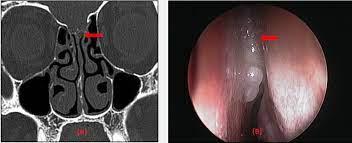

Endoscopic repair is considered the treatment of choice in cerebrospinal fluid

Cerebrospinal fluid (CSF) rhinorrhea has been reported to be spontaneous or secondary to head trauma. The repair of CSF rhinorrhoea has rapidly evolved over the past 30 years. Prior to the advent of the endoscopic approach, craniotomy was used for repairs, which carried a variable success rate and relatively high morbidity

The most common clinical manifestation of CSF leak is clear, unilateral rhinorrhoea, exacerbated by bending over or performing a Valsalva manoeuvreer. The presence of headache should make the clinician suspicious of raised intracranial pressure or or meningitis.

Diagnosis can be confirmed by the laboratory analysis of CSF markers such as Beta-2 transferrin, which is a sensitive and specific marker in chronic or severe cases.

More usually however, a CT Scan or MR Cysternography is performed to diagnose the presence and location of a leak.